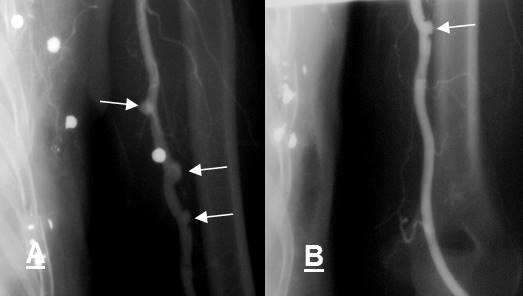

Fig 142 F. Seudoaneurismas múltiples.

A y B: Arteriografía de extremidad superior. Paciente que recibe herida por perdigones. Muestra varias imágenes saculares, que corresponden a seudoaneurismas. (Flechas).